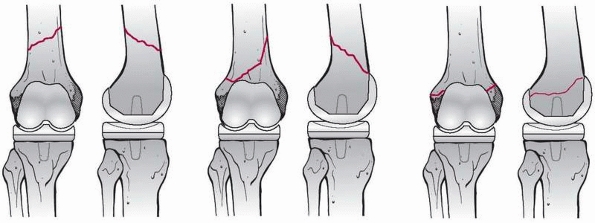

fractures.14,34 It considers the location of the fracture relative to the stem, the stability of the implant, and associated bone loss (Fig. 21-1).

Type A fractures are in the trochanteric region, type B fractures

involve the tip of the stem, and type C fractures are distant to the

tip of the stem such that their treatment is considered independent of

the hip prosthesis. Type A fractures are subdivided into fractures of

the greater trochanter, AG, which are frequently associated with osteolysis and remain stable, and those about the lesser trochanter, AL,

which are more likely to be associated with eventual implant loosening.

Type B fractures are also further subdivided: B1 fractures are

associated with a stable implant, B2 fractures are associated with an

unstable implant, and B3 fractures are associated with bone loss and

usually also a loose implant (Table 21-1).

FIGURE 21-1

The Vancouver classification for periprosthetic fractures about femoral hip arthroplasty stems. Type B fractures are subdivided based on presence of a well fixed stem (Type B1), a loose stem (Type B2), or poor bone stock in the proximal fragment (Type B3). |